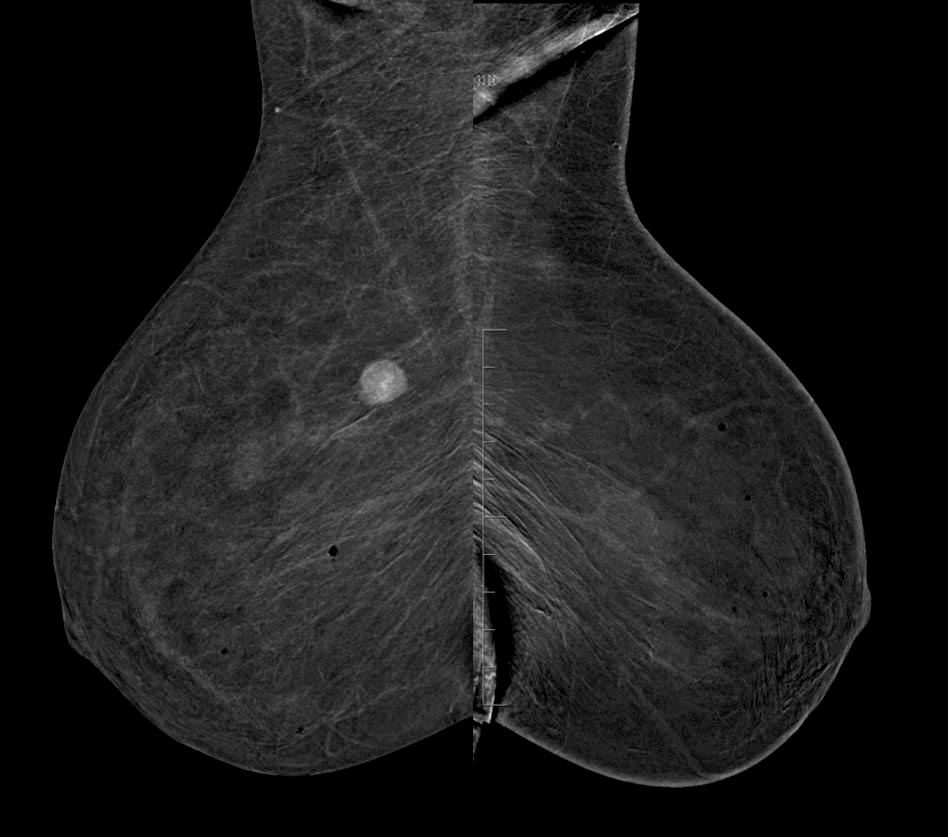

- Control previo en el PPDCMA (Programa de Prevención del Cáncer de Mama en Aragón) en 2019 normal. Control actual en las imágenes.

- A. BI-RADS 0. Hay que completar estudio con RM con contraste.

- B. BI-RADS 1. No hay que hacer nada porque el nódulo tiene aspecto benigno.

- C. BI-RADS 4. Haremos biopsia con aguja gruesa (BAG) del nódulo.

- D. BI-RADS 2. Haremos punción con aguja fina (PAAF) del nódulo.

- E- BI-RADS 3. Control con ecografia mamaria en 6 meses.